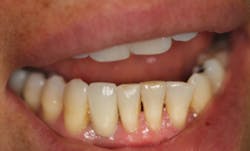

This patient presented with discomfort and mobile teeth Nos. 24 and 25. Extractions were performed, and the area was allowed to heal for six months. Mini-implants were placed in site Nos. 24 and 25 and immediately loaded with temporary crowns. The final splinted restoration was cemented two weeks later.

Figure 9: Implants restored two weeks after placement

Placing narrow-diameter dental implants to replace missing incisors can overcome many of the traditional challenges facing clinicians. Patients with thin ridges and narrow spaces between roots can be restored without using fixed partial bridges or removable prosthetics.